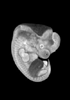

Carnegie Stage 16 (37 post-ovulatory days)

Most embryos at stage 16 are approximately 37 postovulatory days old and measure 11-14 mm in length. Distinguishing criteria for this stage include the external appearance of retinal pigment, the nasal pits face ventrally, pharyngeal arch 2 is more massive and conspicuous than arch 3, auricular bumps begin to appear, and the thigh, leg, and foot can be distinguished in the lower limb.

Animations